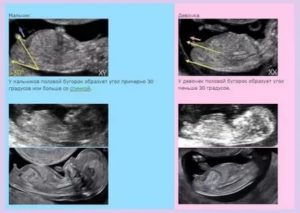

Первый скрининг

Исследование проводят с 10 по 13 акушерскую неделю. Если выбраны оптимальные сроки, на 11-12 неделе беременности, то можно узнать, какой пол у ребенка по половым бугоркам, которые уже обнаруживаются на УЗИ. У девочек центральная ось полового бугорка практически параллельна спинке, а у мальчиков угол между этими воображаемыми осями составляет около 30 градусов.

- Угол, образованный спинкой ребенка и его половым бугорком. На развитие девочки указывает угол менее 30°. Если угол больше – женщина вынашивает мальчика.

Очень опытные УЗИ-специалисты на хорошем аппарате могут определить пол будущего ребенка на 14 неделе. Для этого измеряется угол между половым бугорком и спинкой малыша.

У мальчиков этот угол 300 и больше, а у девочек меньше 300.

- угол между спиной и предполагаемыми половыми органами. Если угол условного треугольника меньше 30 градусов, скорее всего, это девочка, а у мальчиков угол больше;